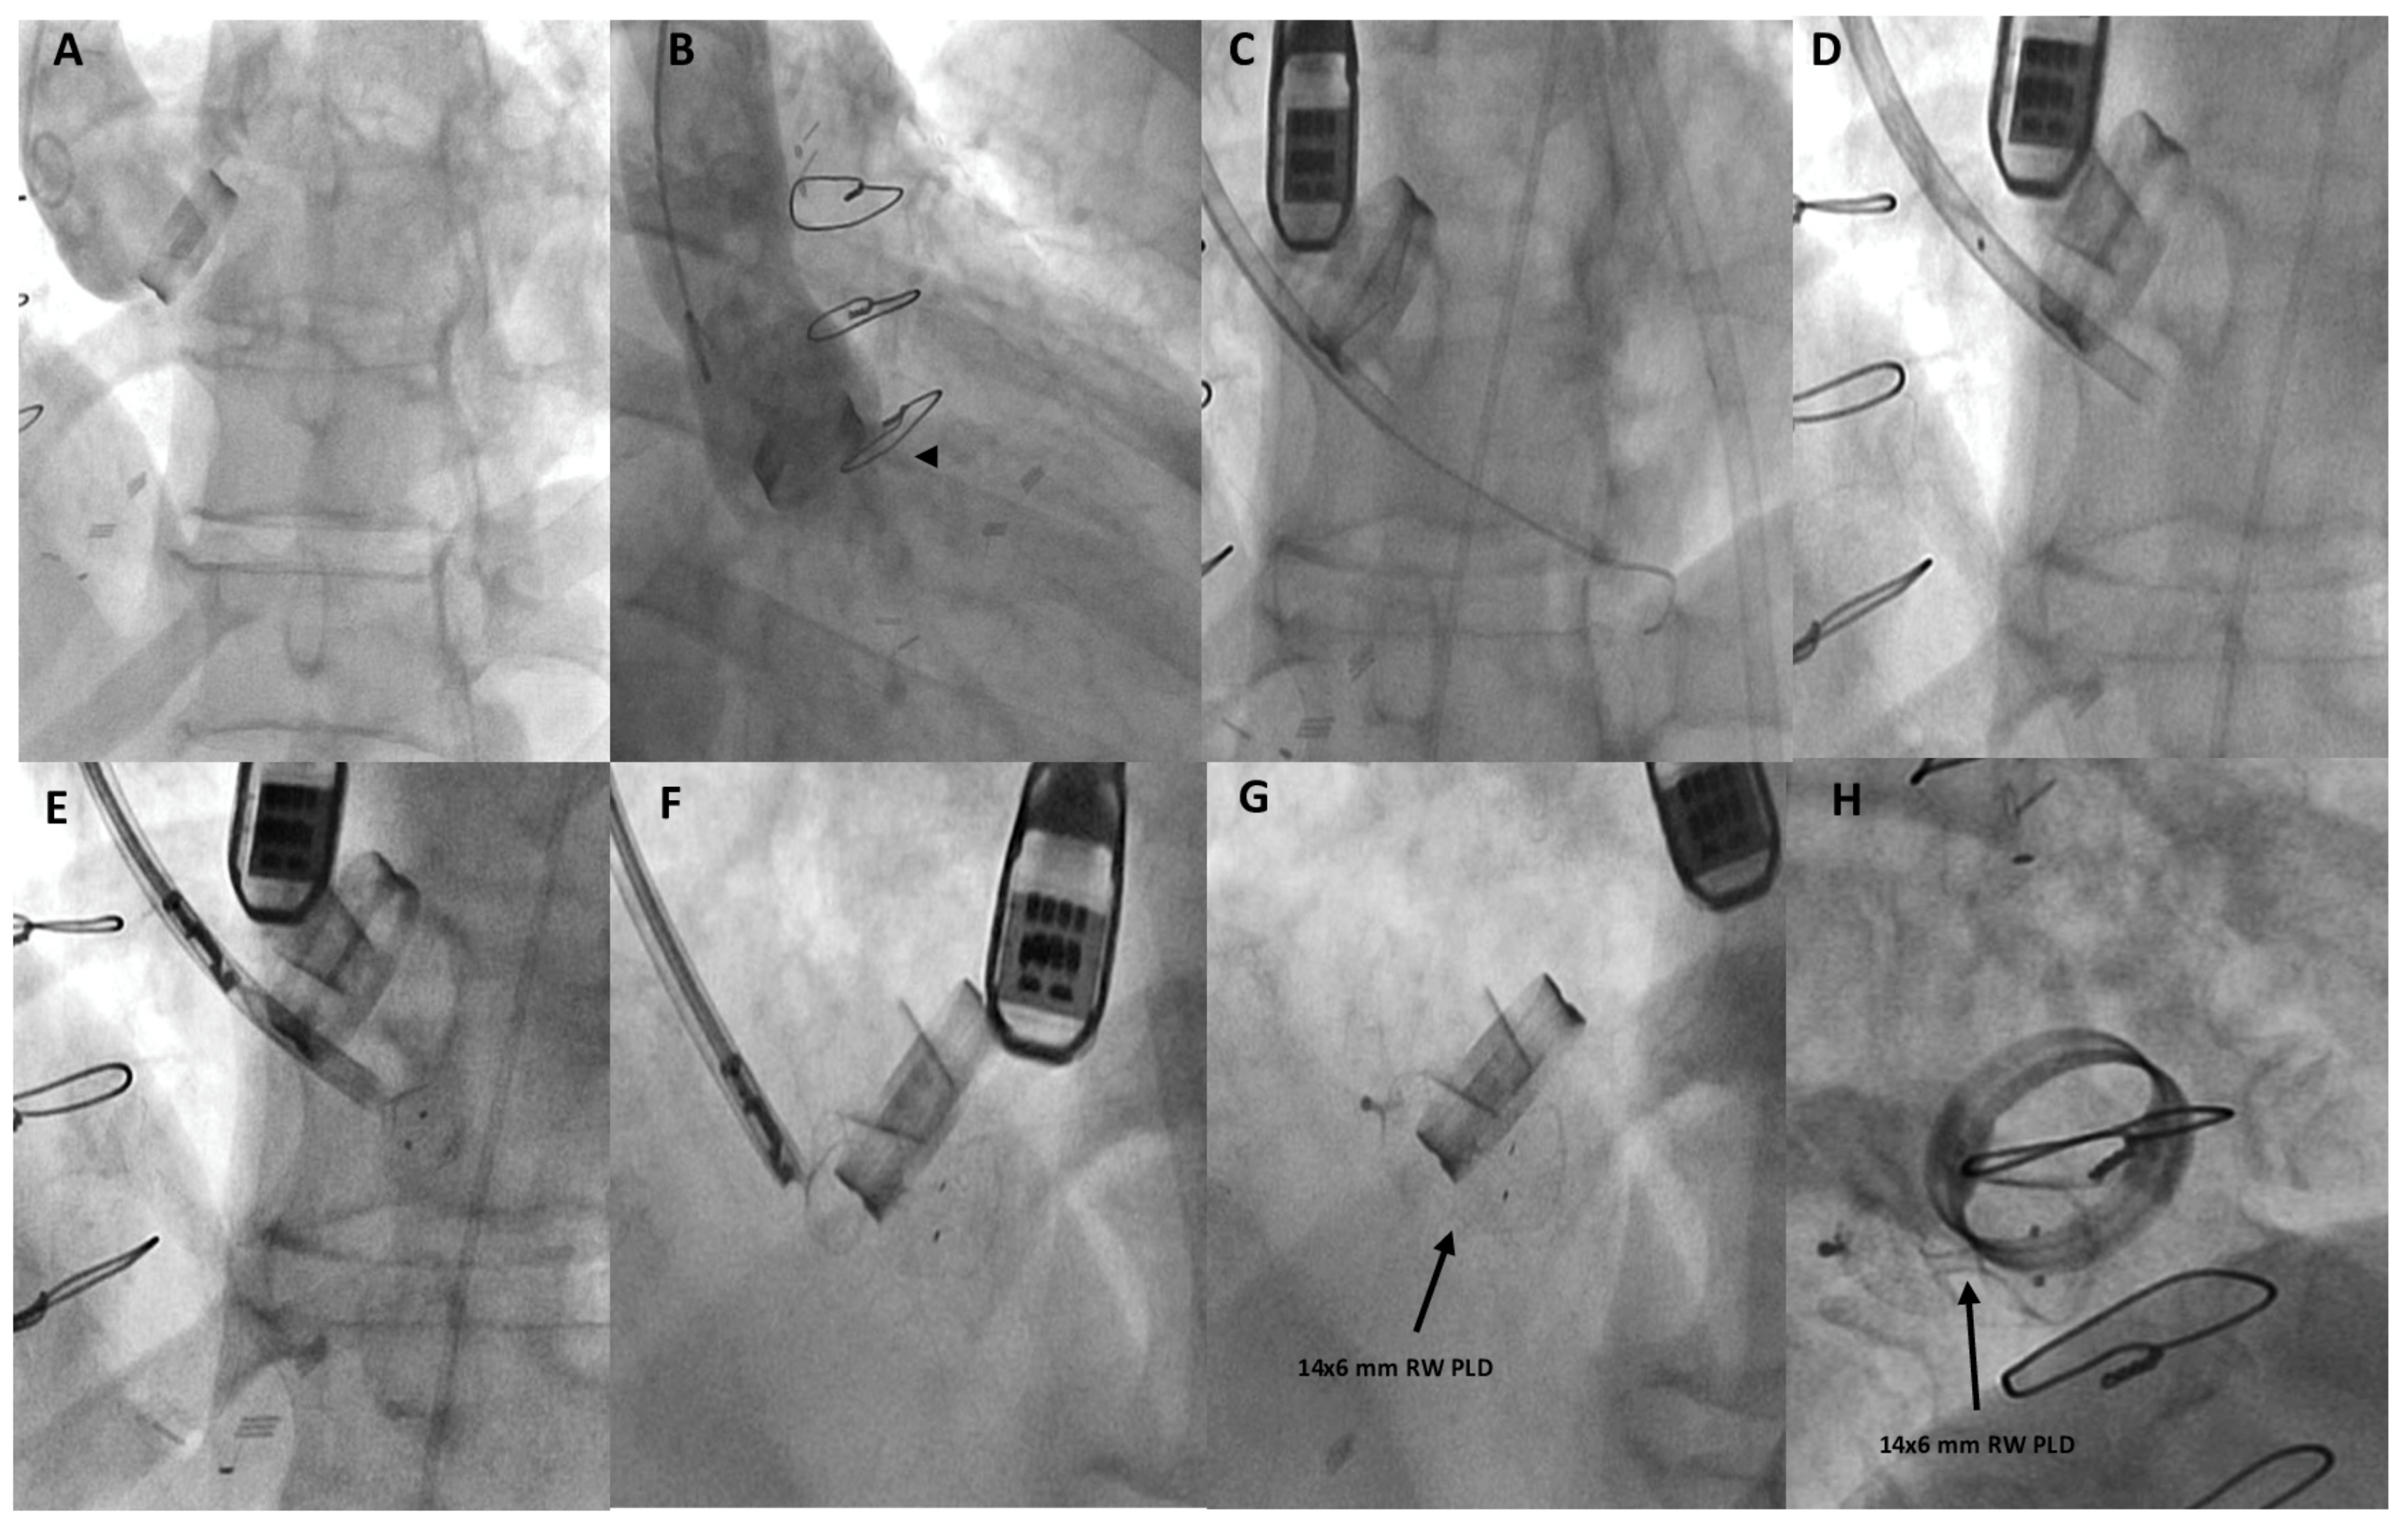

Figure 2.

Fluoro-angiographic procedural steps. Ascending-aorta angiography by a 6-Fr pigtail catheter from the right femoral artery showing paravalvular-leak regurgitation (black arrowhead) (A,B); from left subclavian-artery approach (surgically exposed) a 9-Fr delivery sheath was advanced over the 0.035–260 cm stiff guidewire placed in the left ventricle (C); the distal and proximal discs of the 14 × 6 mm rectangular waist (RW) PLD were then step-by-step advanced (D–F) while still anchored to the delivery system; correct and stable position of the deployed PLD (black arrows) (G,H).